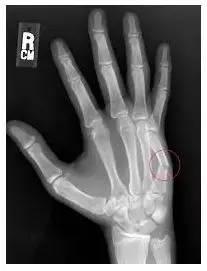

在保罗的案例中,骨间产生不规则的分离,使得骨产生延对角线的下移,从而可能在恢复中使情况更为复杂化。